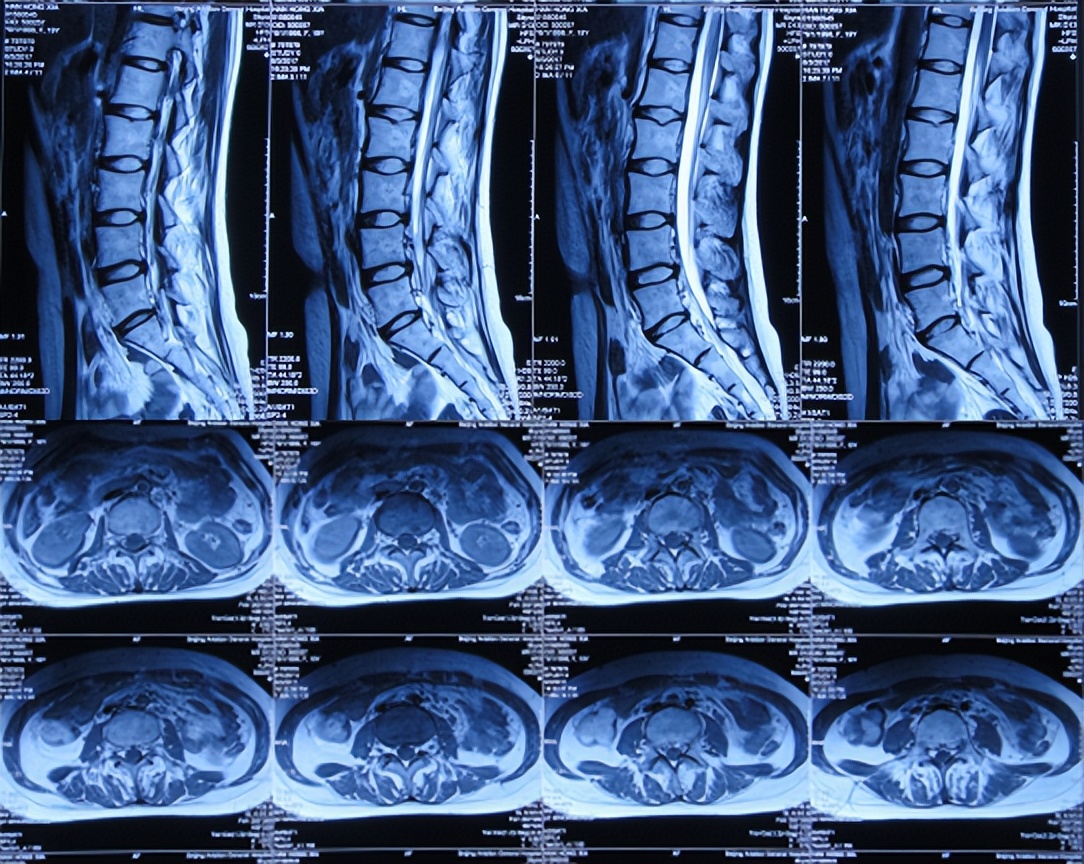

入院治疗77天即2017年8月3日,腰椎核磁示未见明显异常( 图-18 )。

图-18: 2017年8月3日腰椎核磁